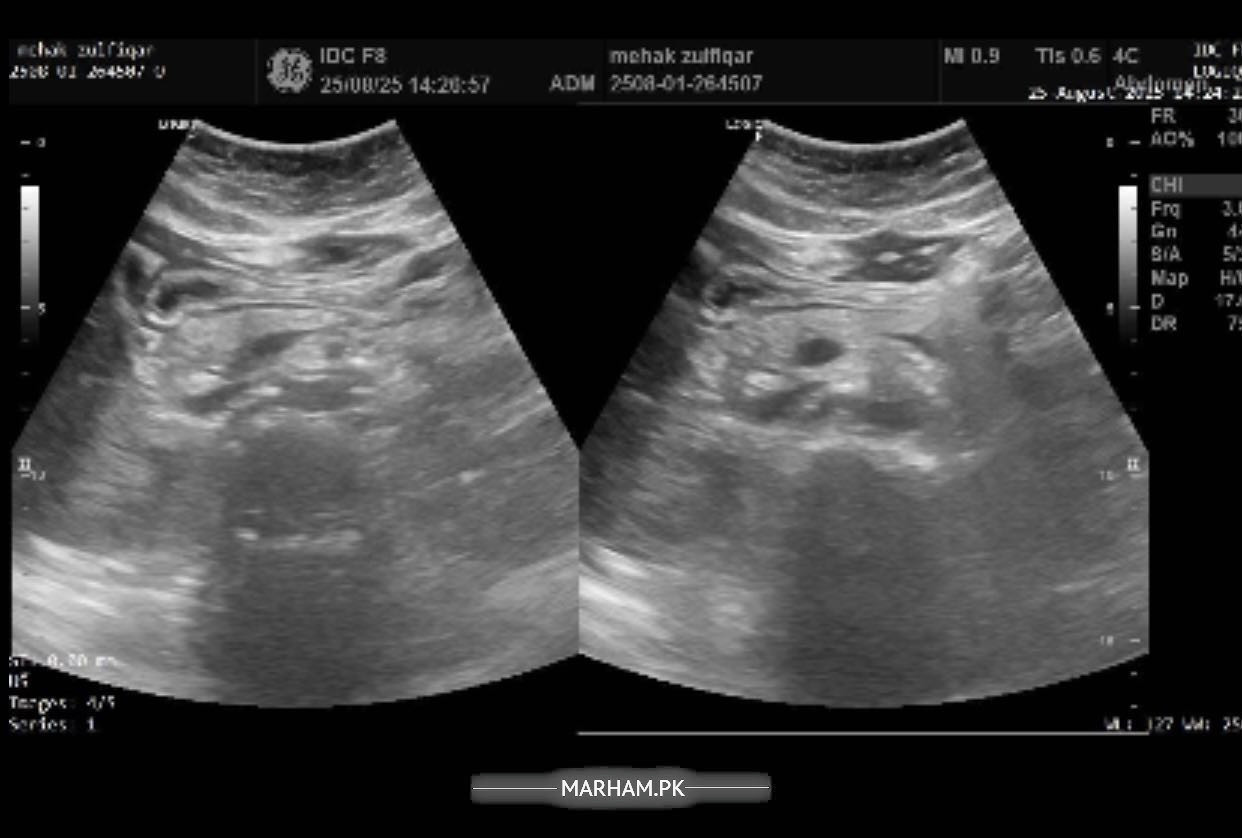

Pain in the right side of abdomen under the ribs followed by backache in the same area. In addition to these symptoms having difficulty concentrating, having confusion, difficulty speaking facial muscles hurt, sleepiness all the time, fluctuations in bp and feel nauseous with sometimes developed fever or shivering. Please help me with this. Will be highly thankful. Attached my reports too.

Sr this is the most recent ultrasound report. But radiology isn’t matching my blood reports. I am worried about that. Pls help.

Sr can’t share pics altogether but here it is

Another

report of ultrasound